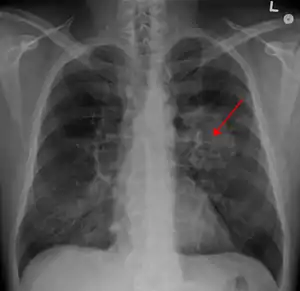

| A chest X-ray showing a tumor in the lung (marked by arrow) | |

Performing a chest radiograph is one of the first investigative steps if a person reports symptoms that may be suggestive of lung cancer. This may reveal an obvious mass, the widening of the mediastinum (suggestive of spread to lymph nodes there), atelectasis (lung collapse), consolidation (pneumonia), or pleural effusion.[15] CT imaging of the chest may reveal a spiculated mass which is highly suggestive of lung cancer, and is also used to provide more information about the type and extent of disease. Bronchoscopic or CT-guided biopsy is often used to sample the tumor for histopathology.[13]

Lung cancer often appears as a solitary pulmonary nodule on a chest radiograph. However, the differential diagnosis is wide. Many other diseases can also give this appearance, including metastatic cancer, hamartomas, and infectious granulomas caused by tuberculosis, histoplasmosis or coccidioidomycosis.[65] Lung cancer can also be an incidental finding, as a solitary pulmonary nodule on a chest radiograph or CT scan done for an unrelated reason.[66] The definitive diagnosis of lung cancer is based on the histological examination of the suspicious tissue[2] in the context of the clinical and radiological features.[12]